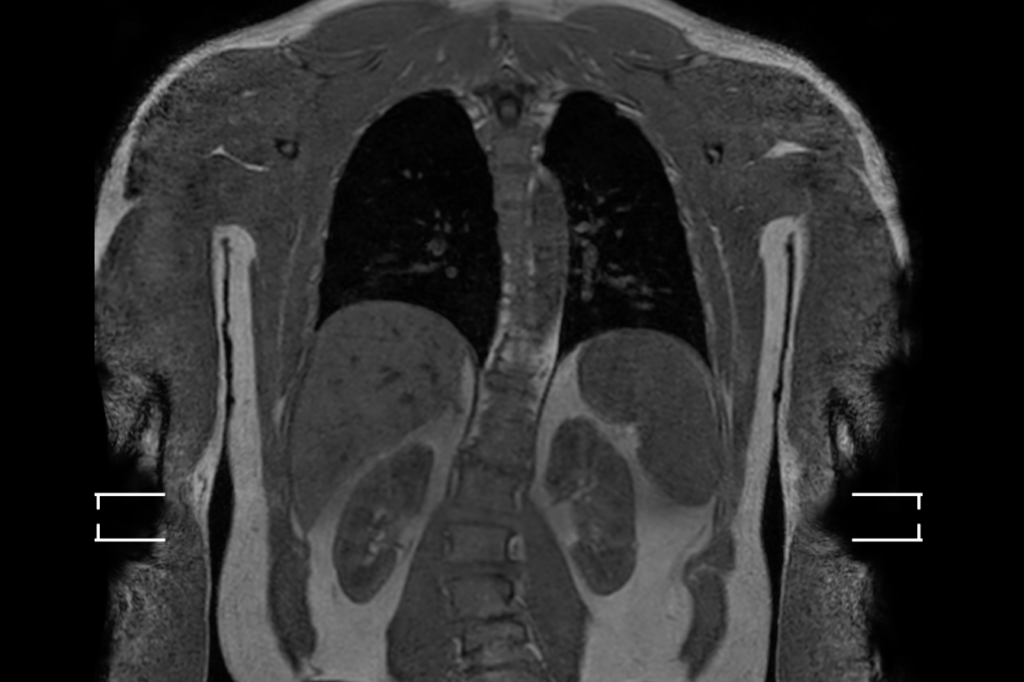

I have nothing to hide from you, Dear Reader, so I’ve included images of my insides with this column. Other journalists may talk a good game about transparency. But how many of them have shown you videos of their spleens?

So I opted for the $1,000 torso scan — still an extravagance, but within reach for more people. It also provides the biggest bang for the buck. “This is our bread-and-butter area,” Modi said, noting that 17 of the 22 cancers detected in the Prenuvo study were in the chest, abdomen or pelvis. This, Modi said, is where they often find cancers that wouldn’t be discovered until they are incurable, like “that scary pancreatic stuff.”

Alongside the written report were a bunch of photographs and videos from the scan that looked like cuts of osso buco and rib-eye. There was a red and squiggly “tumor detection” sequence; a spinning torso in black and blue; a “fat-sensitive sequence” that looked like an amoeba; various videos showing organs, muscles and bones dissolving and reappearing; and one showing my pancreas spinning like a wind sock.